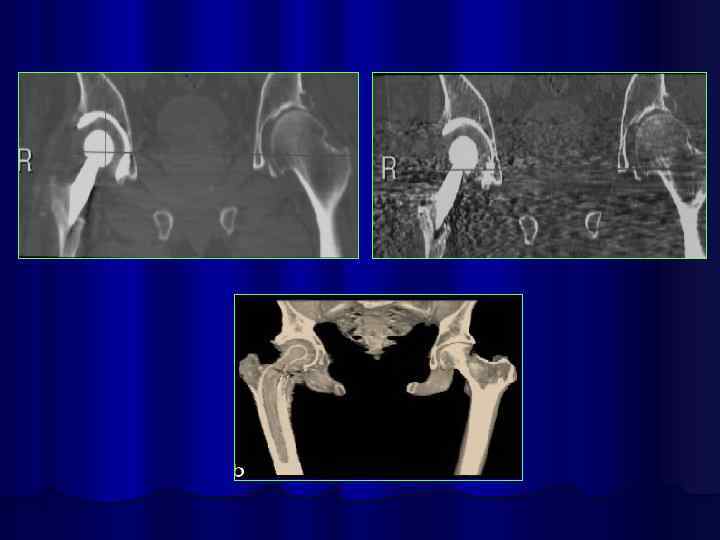

Коксартроз